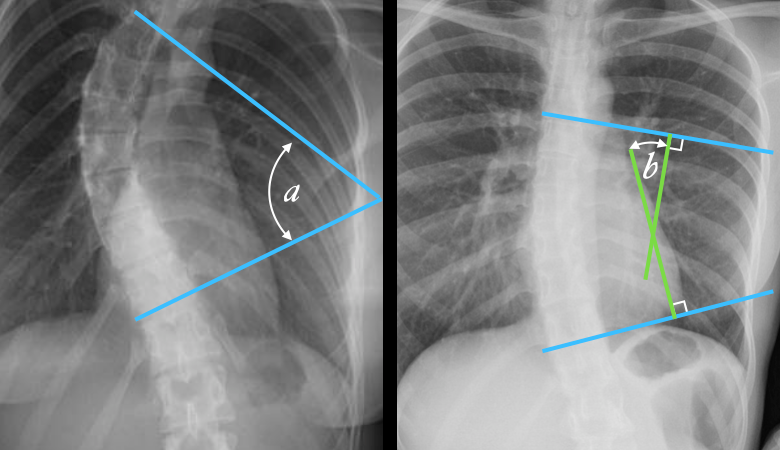

Spinal Biomechanics and Basics of Spinal Instrumentation Article topic: Spinal Biomechanics and Basics of Spinal Instrumentation Author: Yasser Banat Scientific editor : Dr.Omar Jbara Linguistic editor: Zain Alsaddi, phillip ... Yasser BanatFebruary 1, 2021 Neurosurgery